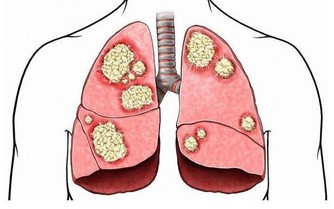

2. 打噴嚏:當我們的呼吸道吸進太多過敏原、微生物、灰塵或其他刺激物時,就會打噴嚏。

這是身體排除掉這些「垃圾」的方式。